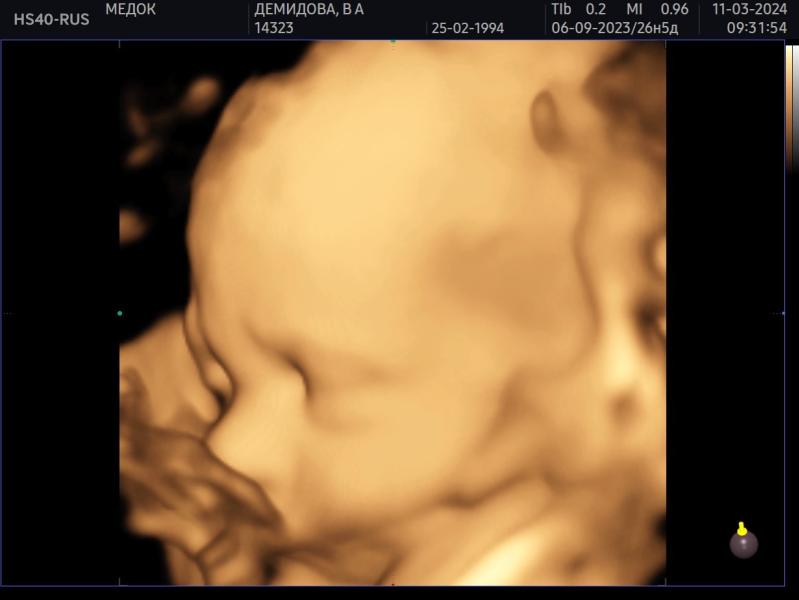

Была сегодня на 3д/4д узи в своей клинике, где веду беременность - Медок Марфино. Узист Лункина ЕГ (вдруг кто тоже туда планирует идти).

Проходила у нее два скрининга, будет у нее же третий, и вот сегодня промежуточное узи.

Срок 27.5 по 1 скринингу, так и опережаем месячные на неделю.

Сын весит около 1163 г. Ваши детки сколько весили на таком сроке?

Врач говорит что хороший вес для этого срока.

В целом все в порядке, лоханки так и остались слегка расширены, но врач сказала это не страшно. ...